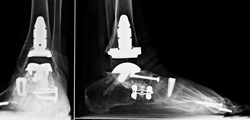

The patient shown in these x-rays had arthritis of the hindfoot. It was treated by fusing all three joints of the hindfoot (triple fusion). An ankle replacement was also done in order to improve mobility and avoid the severe stiffness that would result from another ankle fusion. The ankle replacement implants can be seen here from the front and the side.